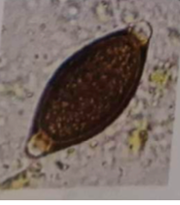

Draw and describe trichuris spp.

- Lemon shape with 2 polar plugs

- 2 thick shells

- Unembryonated

- Brown